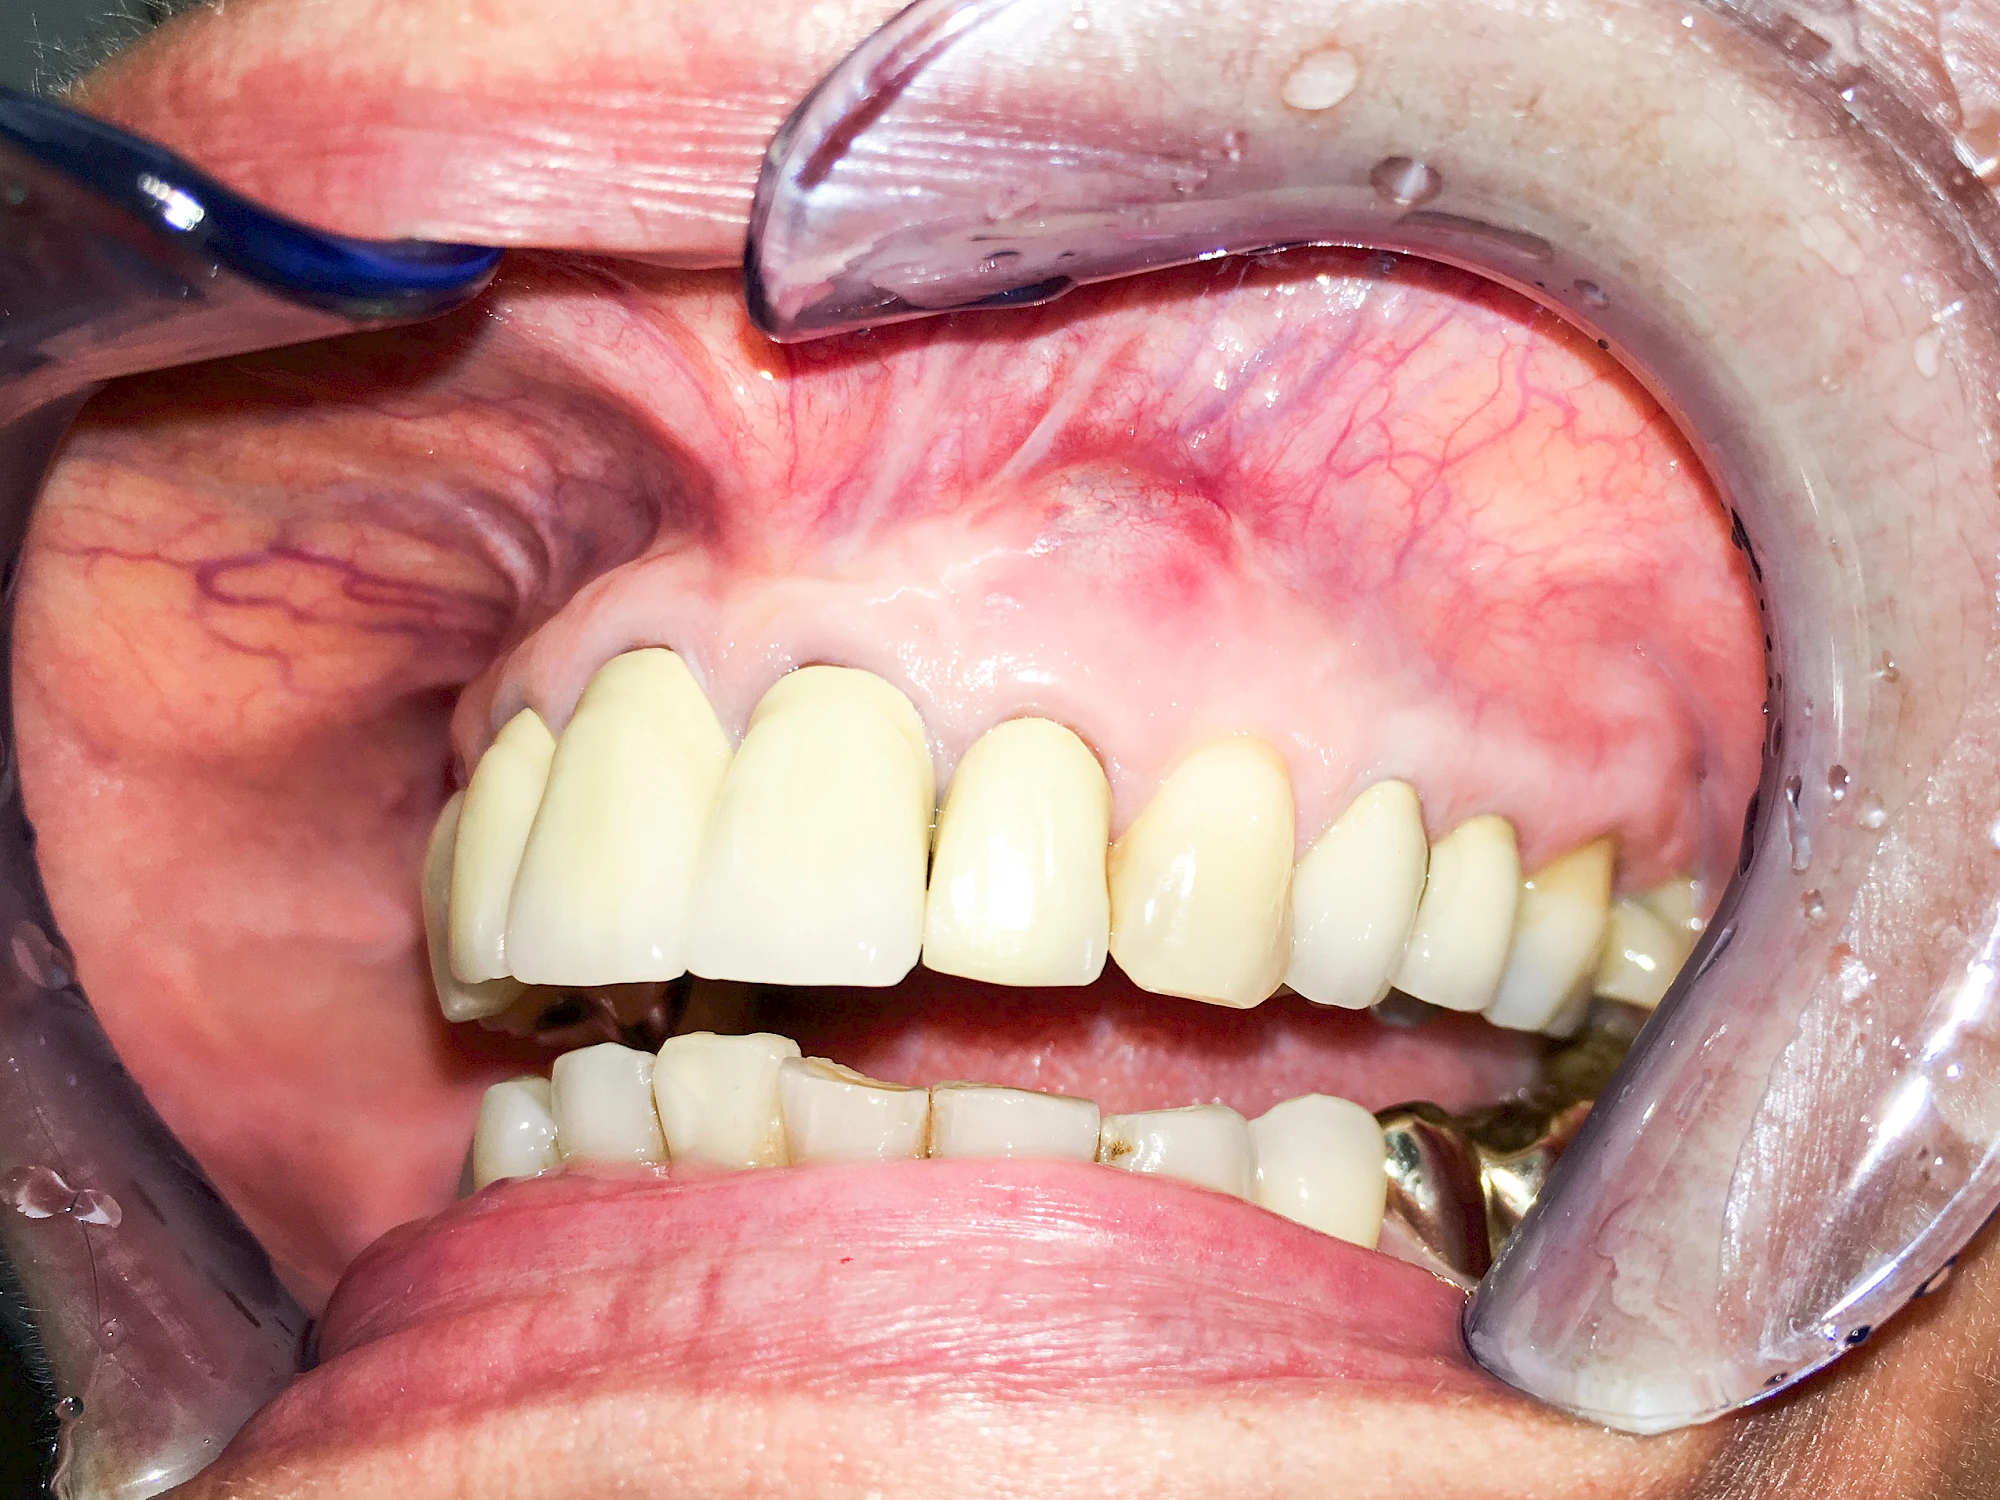

Ist zunächst nur das Zahnfleisch von der Entzündung betroffen, spricht man von Gingivitis. Später, wenn auch der Knochen um die Zähne herum entzündet ist, spricht man von einer Parodontitis. Bei der Parodontitis wird der Knochen nach und nach abgebaut und das Zahnfleisch zieht sich zurück. Die Zahnhälse und Zahnwurzeloberflächen liegen mehr und mehr frei. Die Zähne werden zunehmend lockerer und fallen schließlich aus.

Bei Implantaten – also operativ eingebrachten künstlichen Zahnwurzeln – kann der Körper die Bakterien auch nicht so gut abwehren. Hier spricht man im Fall einer Entzündung von einer Peri-Implantitis, also einer Entzündung um das Implantat herum.